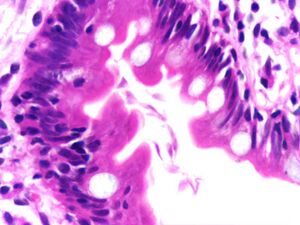

image الإنجليزية